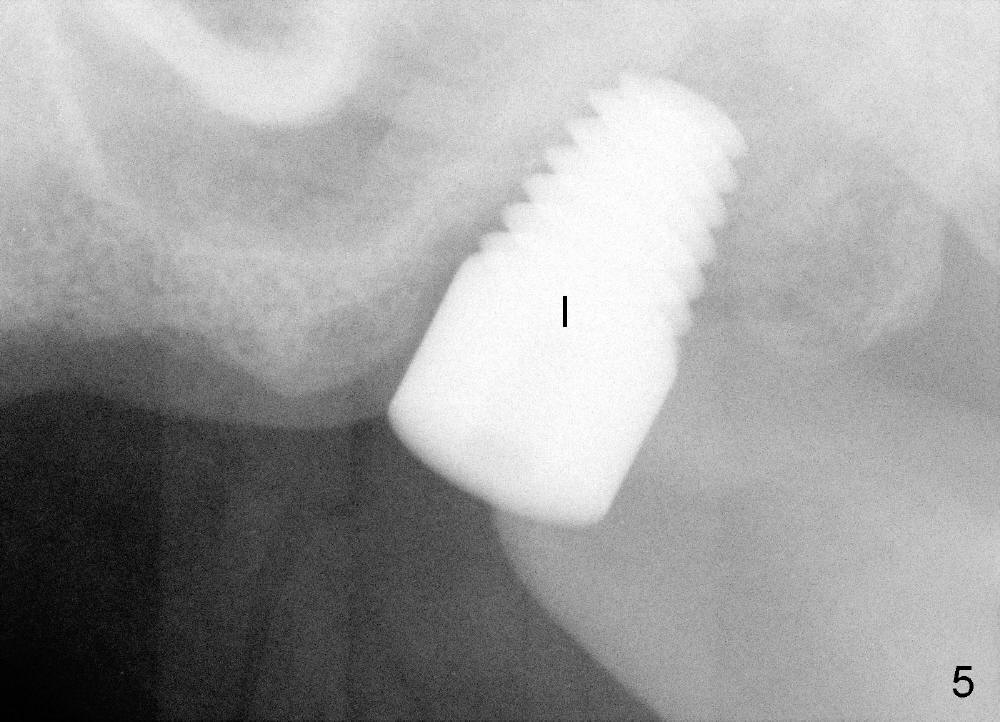

In fact, a tapered tap of 8x14 mm was used (Fig.4 T) before the implant of equivalent size was placed (Fig.5: I). The patient and the implant are doing fine after surgery. No bone loss is noted 4 years 4 months post cementation (Fig.6).